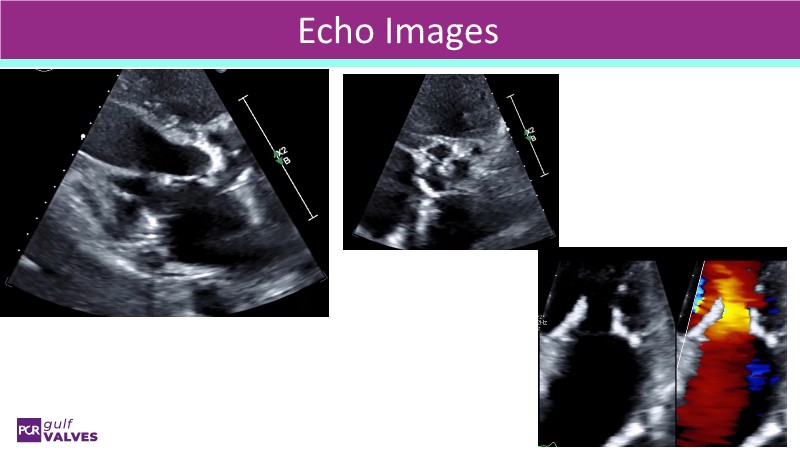

Discover a selection of cases showcasing the key features of the Navitor Valve System and its clinical applications. This session explores auxiliary access, the use of Navitor in alternative access and complex PCI, its performance in challenging peripheral anatomies, and innovative outcomes with the Vantage 30D system.